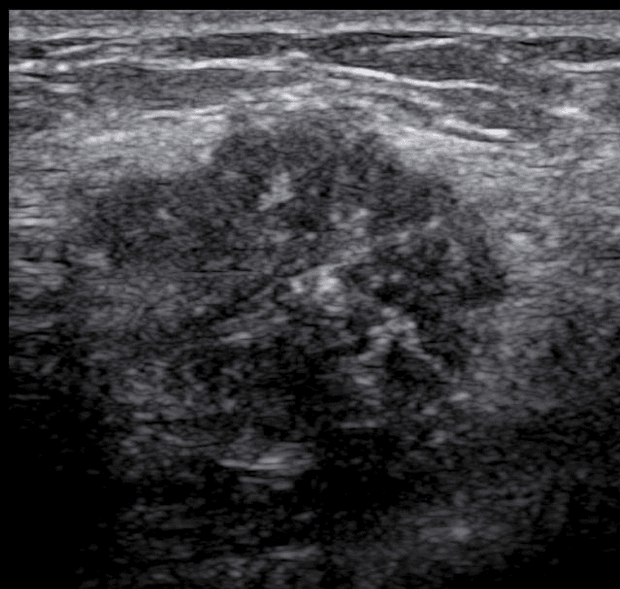

câncer na ultrassonografia de mamas

Ultrassonografia de mamas demonstrando um nódulo provavelmente maligno. Na avaliação anatomopatológica foi confirmado um carcinoma ductal grau 3 (câncer).